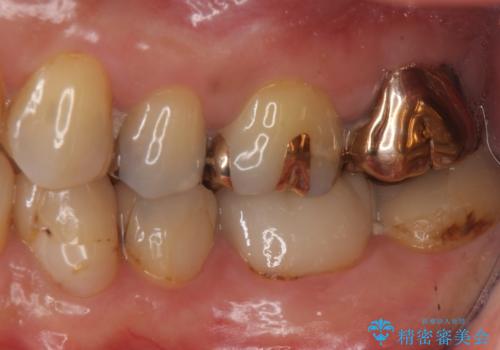

1. 昔いれたクラウンが割れたので金属の被せ物を入れたいの治療前